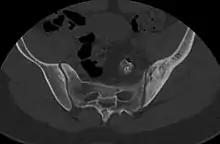

- Nguyen, Nghi; Khan, Mujahid; Shah, Muhammad (2017). "Primary B-cell lymphoma of the pelvic bone in a young patient: Imaging features of a rare case". Cancer Research Frontiers. 3 (1): 51–55. doi:10.17980/2017.51. ISSN 2328-5249.